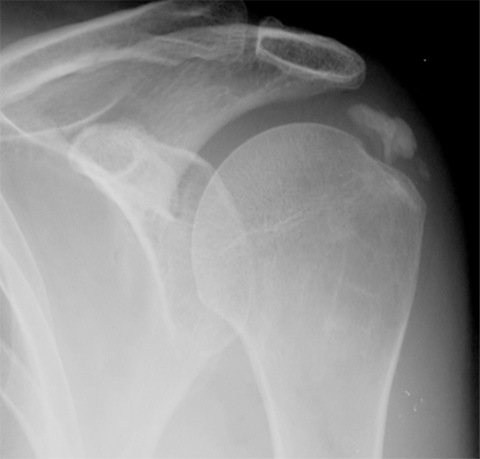

• X-ray

엑스레이에서 어깨 주위에 뼈 음영과 비슷한 밀도의 하얀 석회질이 있는 것이 확인된다. 석회의 위치에 따라서 전후면, 측면, 액와위

엑스레이 사진을 다양한 방향에서 검사해야 합니다.

엑스레이에서 석회질이 확인된다.

- 환자 동의하에 게시된 이미지입니다.